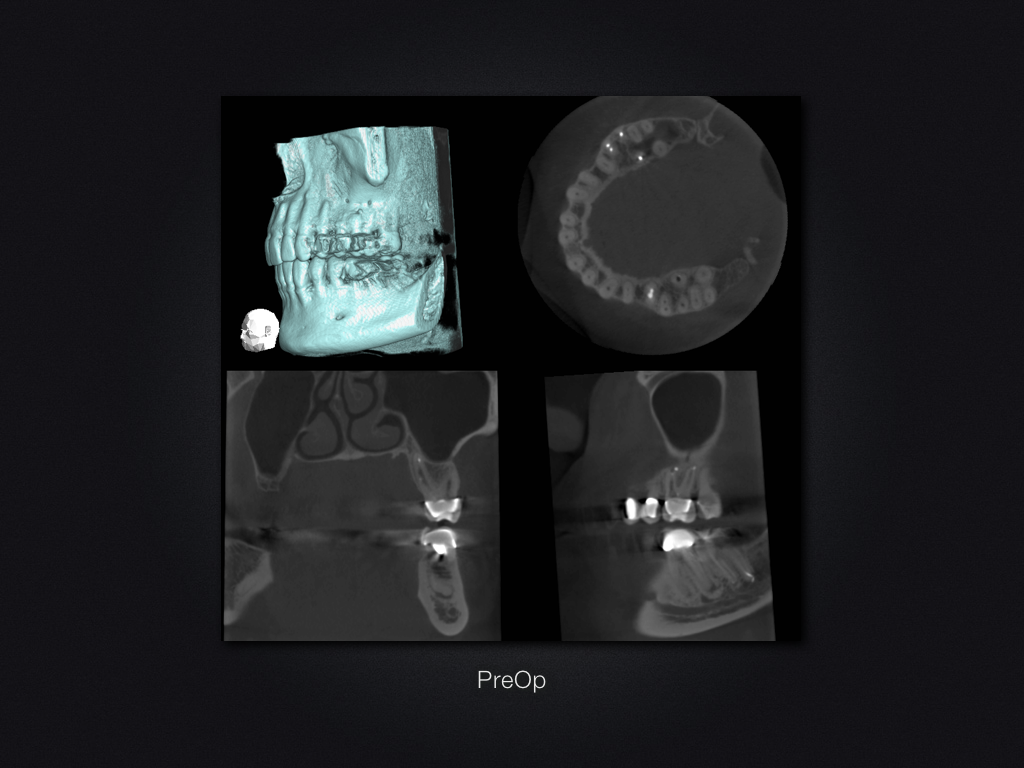

26D.004

Saving Hopeless Teeth (XXXII)